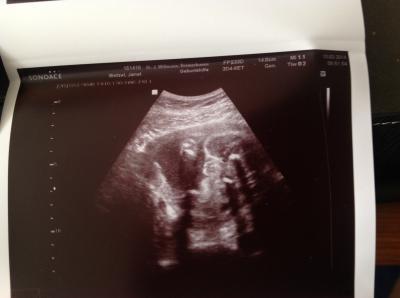

Hallo, So wieder zu Hause. Es ist eindeutig ein Mädchen. freu Alles ok liegt allerdings etwa eine Woche unter dem errechneten Termin was mich nicht beunruhigt denn meine 4 anderen waren der schwerste 2320g bei Geburt. Geschätztes Gewicht jetzt sind 980g Zum ultraschallbild. Oben rechts die Wölbung IST das Knie und die beiden kleineren danach sind die Schamlippen. :) LG

Bild zu Zurück vom Doc - Forum für Mai - Mamis